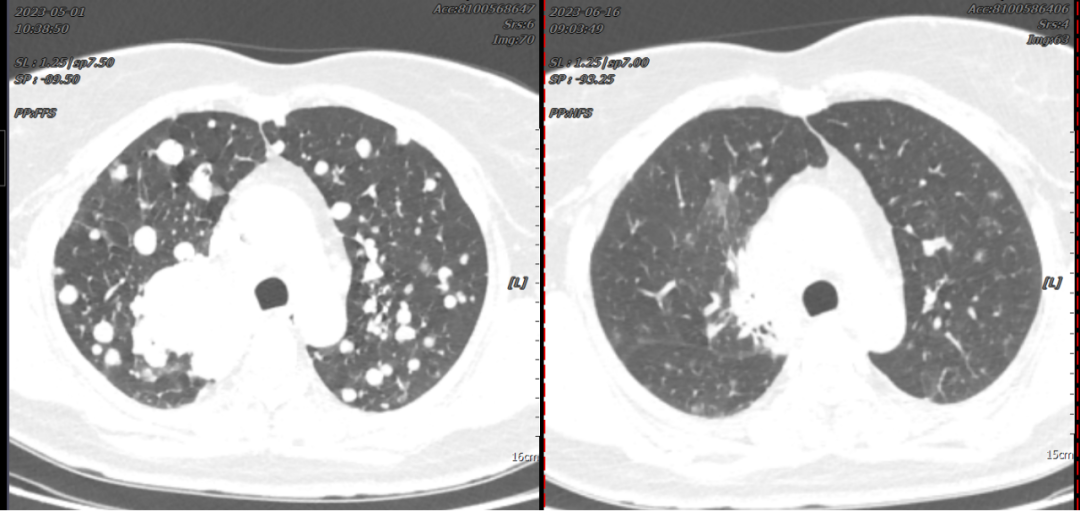

Patient Song XX, female, 41 years old, presented with cough, expectoration, accompanied by chest tightness and shortness of breath. In May 2023, a chest CT scan performed at our hospital revealed a mass near the hilum of the right upper lobe with diffuse multiple nodules distributed in both lungs, stenosis and occlusion of the right upper lobe bronchus, and encasement of the right upper pulmonary artery and brachiocephalic veins, suggesting right lung cancer with bilateral lung metastases. Subsequently, a CT-guided lung biopsy was performed, and pathological examination confirmed right lung invasive adenocarcinoma. Genetic testing showed an EGFR-19Del mutation. The diagnosis was "right lung adenocarcinoma, driver gene-positive (EGFR-19Del mutation)." After oral targeted therapy, the patient's cough, chest tightness, and shortness of breath significantly improved. A follow-up chest CT one month later showed significant shrinkage of the lung lesions, with most tumors gradually disappearing. The clinical efficacy was evaluated as PR (Partial Response).